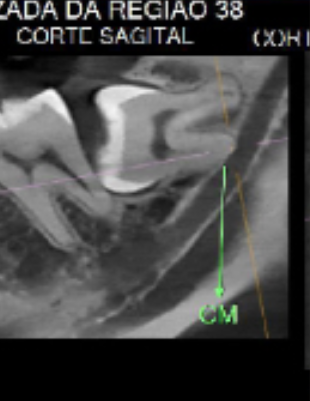

Veja alguns casos de sucesso